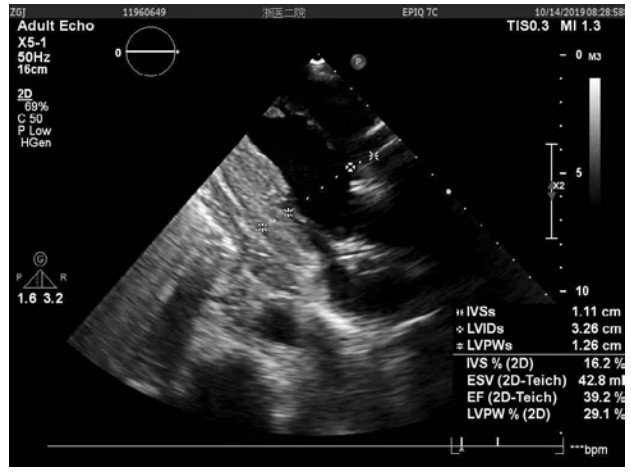

患者行Impella支持期间每日心超提示:左心功能逐步恢复。至辅助第5天时,LVEF达到39%。第9天,血管活性药减停,患者生命指征平稳,心脏基础瓣膜疾病以及ICU机械通气时间较长导致的肺部感染已基本控制。心超示EF约为35%~40%。达到撤机指征,撤除Impella。41 d后,患者于2019年10月18日康复出院,心超(图 2)示LVEF 35.8%,LVEDV 110 mL,LA 3.37 cm。出院后2个月心超(图 3)随访,LVEF 41.1%,LVEDV 85.7 mL。

| 图 2 患者康复出院日心脏超声结果 |